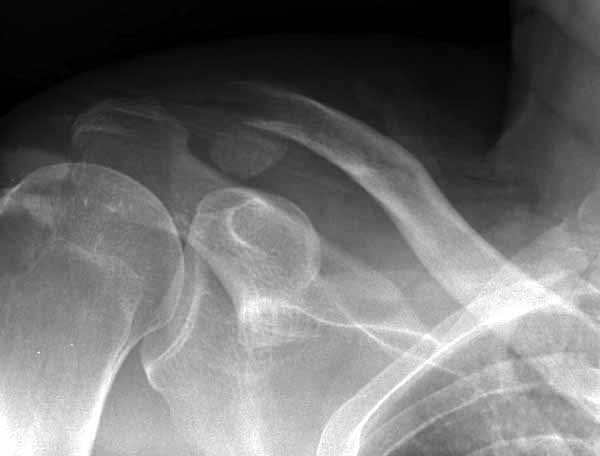

foto 4

4.JPG

14KB (14434 bytes)